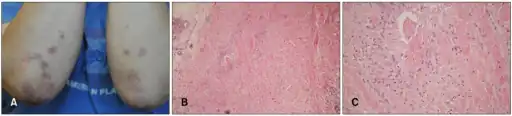

Histological examination of nodules shows that they consist of a shell of fibrous tissue surrounding a center of fibrinoid necrosis.[13] Pea-sized nodules have one centre. Larger nodules tend to be multilocular, with many separate shells or with connections between the necrotic centers. Individual necrotic centers may contain a cleft or several centers of necrosis may all open on to a large bursal pocket containing synovial fluid.

The boundary between the necrotic center and the outer fibrous shell is made up of the characteristic feature of the nodule, which is known as a cellular palisade. The palisade is a densely packed layer of macrophages and fibroblasts which tend to be arranged radially, like the seeds of a kiwifruit or fig.[13] Further out into the fibrous shell there is a zone that contains T cells and plasma cells in association with blood vessels.[14] The histology of pulmonary nodules are similar to that of subcutaneous nodules, with central necrosis surrounded by palisading macrophages and inflammatory infiltrate.[5]